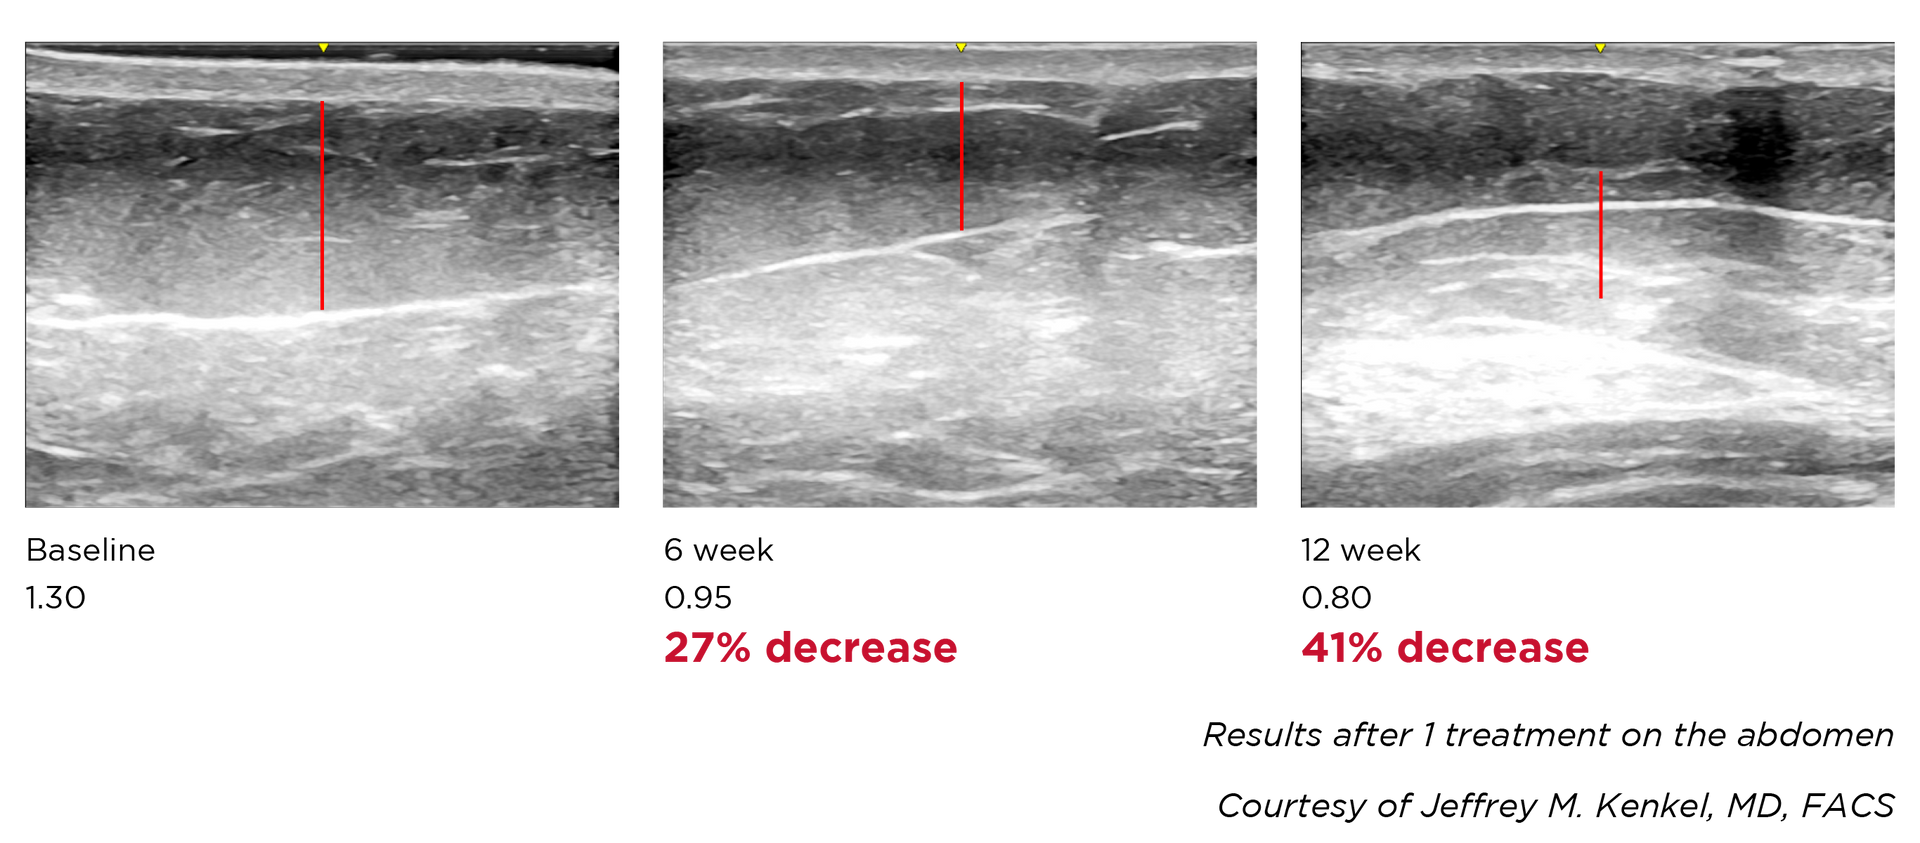

Non-surgical radio frequency treatments provide a rejuvenating effect

on the skin by safely and comfortably heating the tissue beneath the

skin's surface. This process stimulates the natural production of

collagen and elastin, the essential building blocks for maintaining

healthy and youthful skin. The outcome is effortlessly tighter,

smoother, and more youthful-looking skin.